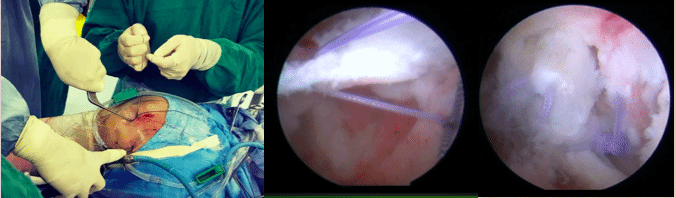

国际首创关节镜下关节囊提拉紧缩术,可提高髋关节微不稳及临界髋关节发育不良患者术后关节稳定性,提高关节囊术后愈合率的同时提升关节囊张力,通过软组织手术实现增加髋关节整体稳定性。